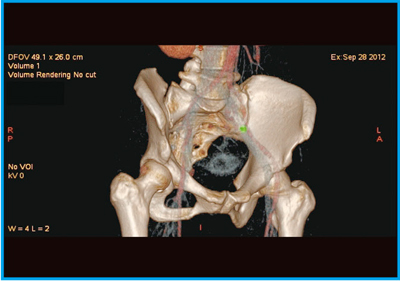

●症例1:前立腺がん骨移転の89Sr image

図1に,前立腺がん骨移転の89Sr imageを示す。集積があることはわかるが,これだけでは解剖学的にどこに集積しているかはわからない。そこで,CTとフュージョンすると,右腸骨に骨転移していることが明瞭に認められる(図2)。さらに,CTの3Dボリュームレンダリング(VR)画像を作成してフュージョンすると,89Srの集積の分布を一目で把握することができる(図3 a)。骨シンチグラフィ(図3 b)の集積部分ともほぼ一致しており,このような画像を示すことで,治療効果に対する患者の理解を促すこともできる。

図3 症例1:SPECT/CTフュージョン3D画像(a)と骨シンチグラフィ(b)